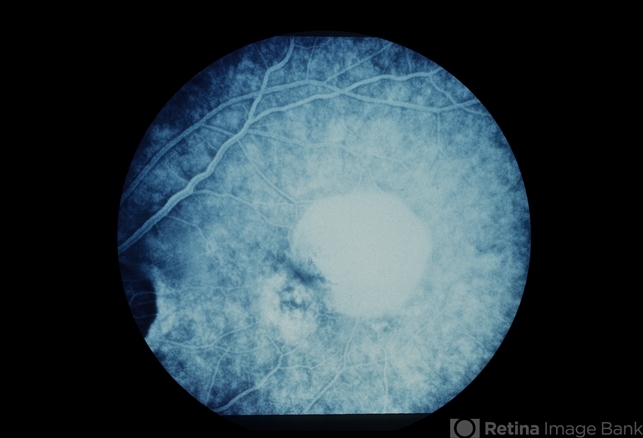

Subretinal fluid in ARMD

- ARMD with CNV and adjacent RPED